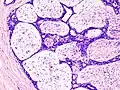

Macroscopic view of fibroadenoma of the breast

Closeup of a fibroadenoma of the breast

Approximately 90% of fibroadenomas are less than 3 cm in diameter. However, these tumors have the potential to grow reaching a remarkable size, particularly in young individuals. The tumor is round or ovoid, elastic, and nodular, and has a smooth surface. The cut surface usually appears homogenous and firm, and is grey-white or tan in colour. The pericanalicular type (hard) has a whorly appearance with a complete capsule, while the intracanalicular type (soft) has an incomplete capsule.[9]